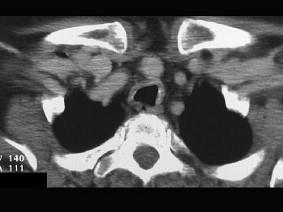

问题 男性,50岁,声音嘶哑近一年,近来感呼吸困难,CT扫描如图所示,请选择正确的描述和结论 ( )

选项 A、考虑为喉气管淀粉样变性 B、考虑气管结核 C、气管后方见软组织肿块 D、肿块内可见致密钙化影 E、喉、气管壁增厚

答案 ACDE